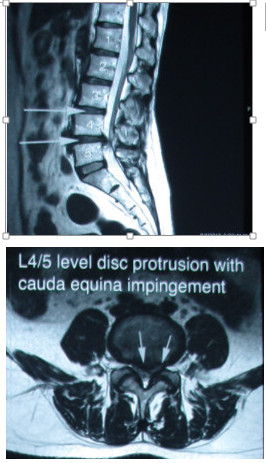

但由於李女士椎間盤突出個案已作了六個月保守性物理治療,加上她有左腳乏力及晚間輕微尿頻現象,所以決定再作磁力共振確認情況。從當日所拍的磁力共振片子,發現她的腰第4、5節椎間盤已突出達0.9公分,壓向馬尾神經線的情況也比之前更甚(見圖二),同時李女士的椎間盤突出已明顯出現神經缺損現象,故建議她應作手術切除突出椎間盤。李女士在2017年1月15日接受了微創切除突出椎間盤手術,術後她先前的腰腿痛、乏力等情況大大改善。

(圖二) 2017年1月腰L4/5椎間盤嚴重突出, 0.9cm壓向馬尾神經線